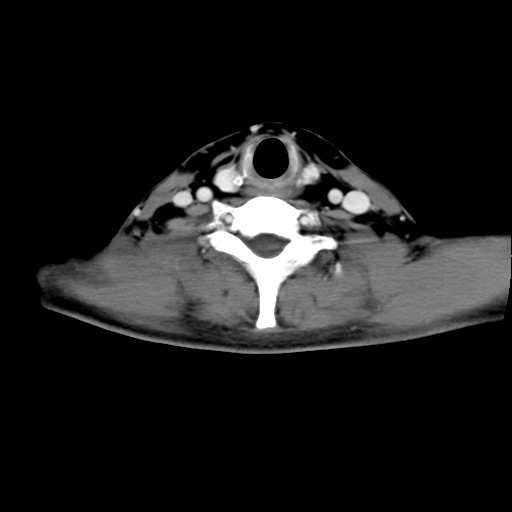

标题: CT24019:男,45岁,发现颈部肿物5个月。 [打印本页]

男,45岁,发现颈部肿物5个月,彩超示:双侧颈部及下颌部软组织增厚。

考虑双侧颈项部良性对称性脂肪增多症。